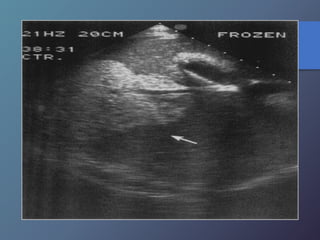

Traumatismo Hepático

• La lesión hepática es a predominio del lóbulo derecho.

• Mayor particularidad en segmento posterior.

• Mayor frecuencia por laceración peri vascular.

• Se producen hematomas subcapsulares,

pericapsulares o aislados.

• La hemorragia en las primeras 24 horas es ecogénica y

posteriormente se hace mas hipoecogénica.

• Entre las dos o tres semanas se puede observar gran

cantidad tejido de granulación.

Traumatismo Hepático • Lalesión hepática es a predominio del lóbulo derecho. • Mayor particularidad en segmento posterior. • Mayor frecuencia por laceración peri vascular. • Se producen hematomas subcapsulares, pericapsulares o aislados. • La hemorragia en las primeras 24 horas es ecogénica y posteriormente se hace mas hipoecogénica. • Entre las dos o tres semanas se puede observar gran cantidad tejido de granulación.